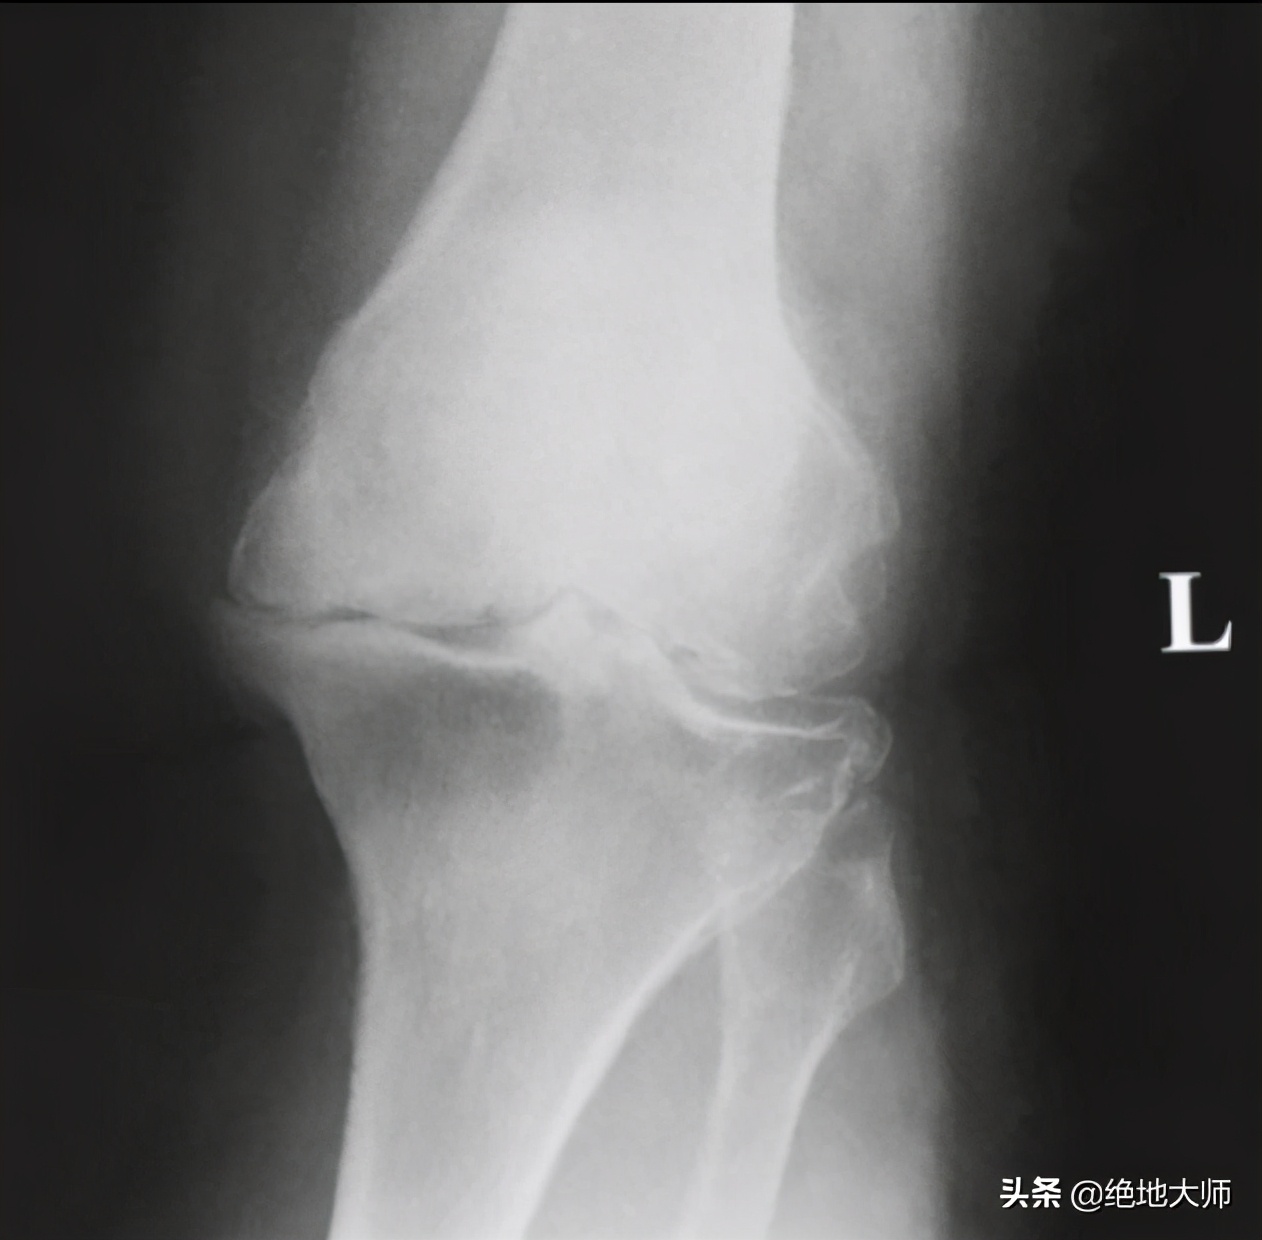

5. OSTEOARTHITIS 骨性关节炎

Joint changes (arthritis) 关节改变(关节炎)